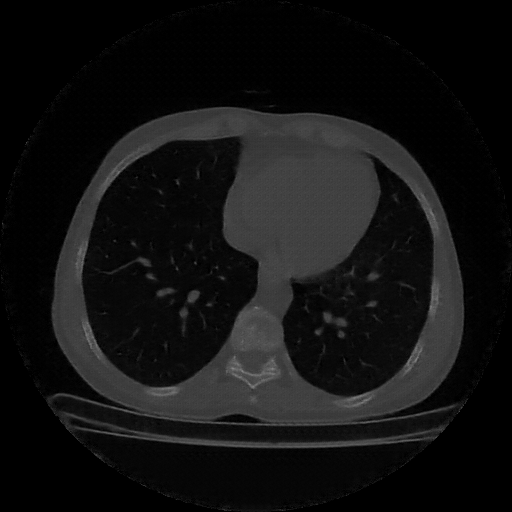

Image Grid

4×3 grid: Rows show different image types (Original NATIVE, Reconstructed NATIVE, Original VENOUS, Generated VENOUS), Columns show windowing techniques (No Window, Lung Window, Mediastinum Window)

Generated VENOUS CT scan (A→B translation)

No window - Raw intensity values

Generated VENOUS CT scan (A→B translation)

Lung window (WL -600, WW 1500 → Low −1350, High +150)

Generated VENOUS CT scan (A→B translation)

Mediastinum window (WL 40, WW 400 → Low −160, High +240)

Windowing Parameters

- No Window: Raw intensity values without windowing

- Lung Window: WL -600, WW 1500 → Low −1350, High +150 (optimal for pulmonary structures)

- Mediastinum Window: WL 40, WW 400 → Low −160, High +240 (optimal for soft tissues)